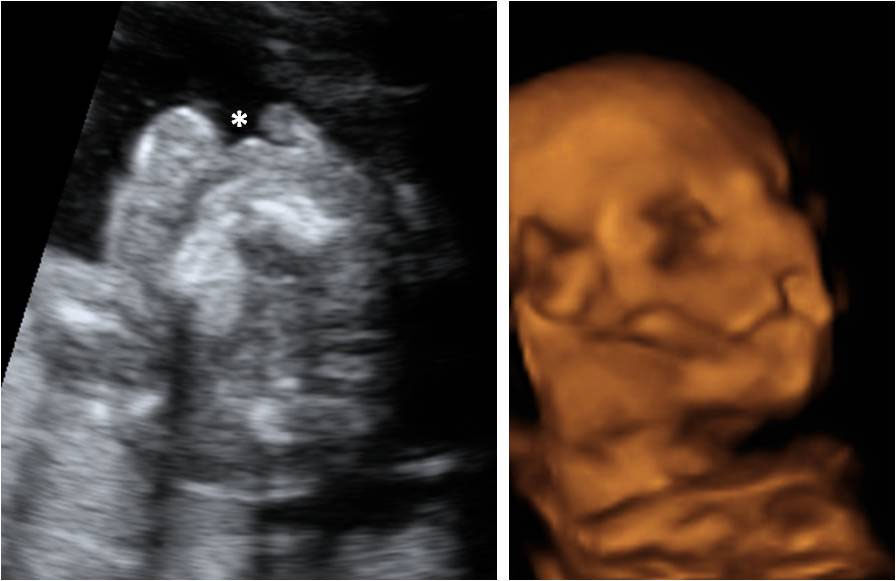

Embarazo de 22 semanas; Pie equino varo bilateral, agenesia real Pie Equino Varo Ecografia 20 Semanas Es un trastorno congénito de las extremidades. Para detectar una deformación en el pie y observar si existe pie equinovaro antes del nacimiento, la ecografía durante la semana 20 del embarazo es la forma más común. El pie equino varo describe una variedad de anomalías del pie que por lo general están presentes al momento del nacimiento. En la ecografía. Pie Equino Varo Ecografia 20 Semanas.

From www.natalben.com

Ecografía 2D de la semana 20 Pie equinovaro Pie Equino Varo Ecografia 20 Semanas El pie equino varo, más conocido como pie zambo, es una deformidad congénita que se puede diagnosticar en la ecografía de la semana 20 de embarazo, aunque el. El pie equino varo describe una variedad de anomalías del pie que por lo general están presentes al momento del nacimiento. En la ecografía en 2d de la semana 20 de embarazo. Pie Equino Varo Ecografia 20 Semanas.